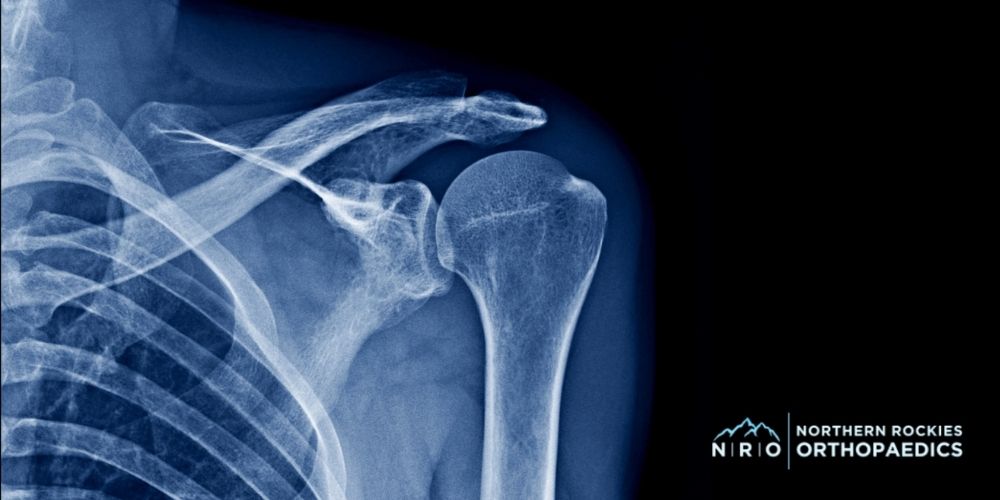

Dislocations and Fractures

Falls, sports accidents, or sudden trauma can cause shoulder dislocations or fractures. A dislocation happens when the upper arm bone pops out of the shoulder joint, while a fracture involves a break in one of the bones. Both injuries can lead to severe shoulder pain, swelling, and an inability to move the arm.

An X-ray of the shoulder joint can reveal the exact location of the injury, which is important when determining the proper treatment plan. Treatment may include bracing or casting, activity modification, and physical therapy to help restore the shoulder’s range of motion and prevent future dislocations. Severe injuries may require surgery to repair tendons, bones, or surrounding tissue.